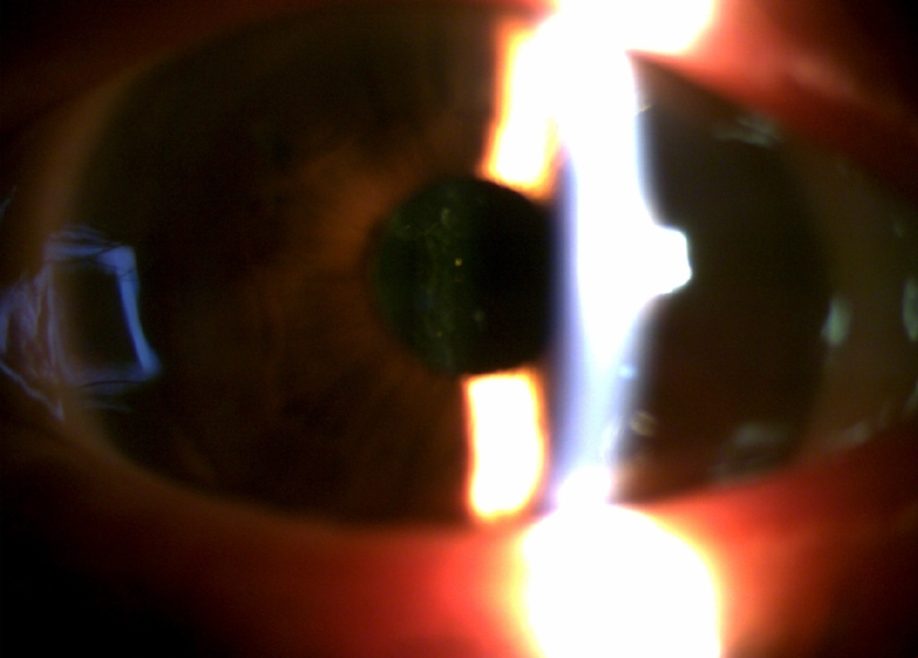

인공수정체 탈구 : 칸나브라바 공막고정수술

54세 남성 환자 사례

수술 8개월 후 나안시력 0.9

54세 남성 환자 사례

수술 8개월 후 나안시력 0.9

수술 전

수술 후

※ 해당 이미지는 본원에서 직접 촬영한 사진입니다.